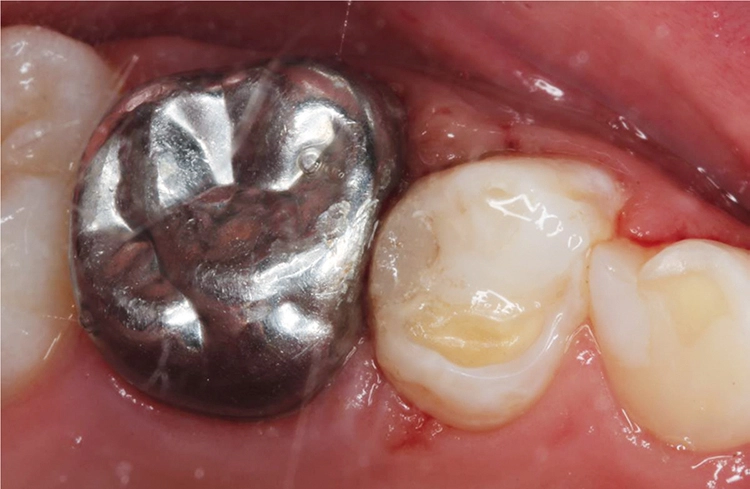

Möhn, KrämerHierfür wurde die Kavität zunächst mit einem birnenförmigen Diamanten aufgezogen und das kariöse Dentin mit einem Polymerbohrer schonend exkaviert (Abb. 3). Für die Formgebung und den Schutz des Nachbarzahnes wurde das Teilmatrizensystem Palodent® V3 verwendet (Abb. 4). Im Anschluss folgte die Füllungstherapie mittels Surefil one™ in Farbe A2.

Möhn, KrämerHierzu wurde das Kapselpräparat per Hand auf einer stabilen Unterlage aktiviert und für 10 Sek. in einem Kapselmischer vermischt. Die Applikation des selbstadhäsiven Materials in die Kavität erfolgte in einem Schritt (Abb. 5).

Möhn, KrämerDank der modifizierten Polysäuren des verwendeten Komposithybrids konnte auf eine adhäsive Vorbehandlung des Zahnes verzichtet werden. Anschließend wurden die Überschüsse mittels Kugelstopfer entfernt (Abb. 6) und jede Fläche für 20 Sek. polymerisiert (SmartLite® Pro).